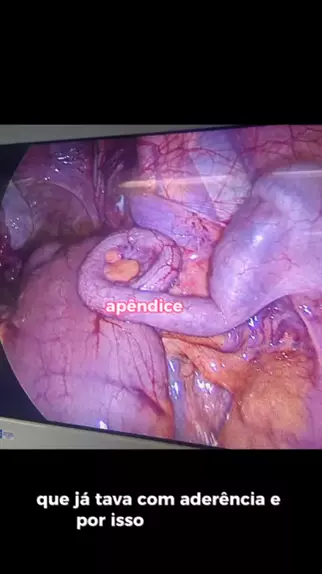

#tratamento #dorcronica #Dor #fy #fy🖤❤